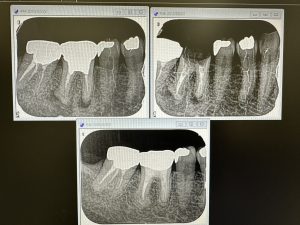

もうひとつの症例は、根充後7年経過、病巣の消失💪

ネチネチ、チマチマ、ストーカー系治療分野、諦めずに、長さ計り、殺菌し薬剤の浸透を心掛ければ誰でも可能、所詮ストレート根は簡単